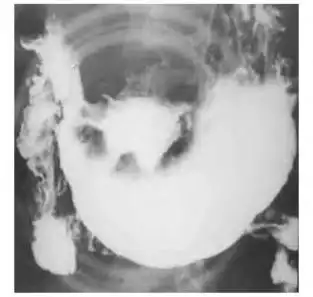

由于炎症肿胀,正位观龛影周围常出现环形透光区称为月晕征(图5-23),其

龛影位于胃轮廓之内,龛影外围绕以宽窄不等的透明带即 环堤,轮廓不